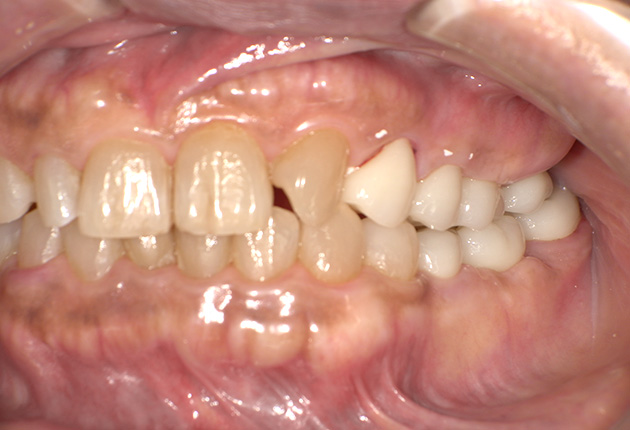

よく噛めず笑うと銀歯が目立つので気にされていました。

| 主訴 | ブリッジ脱離、しっかり噛めない |

| 診査診断 | 上顎歯牙欠損、歯周病、不良補綴、根尖性周囲炎。 不正咬合により噛み合わせのバランスが悪い事が原因により咬合治療が必要。 |

| 治療内容 | 欠損部インプラント 不正咬合に対し不良補綴のやり直しと合わせて咬合再構築 |

| 治療期間 | 4ヶ月 |

| 費用 | 200万円 |